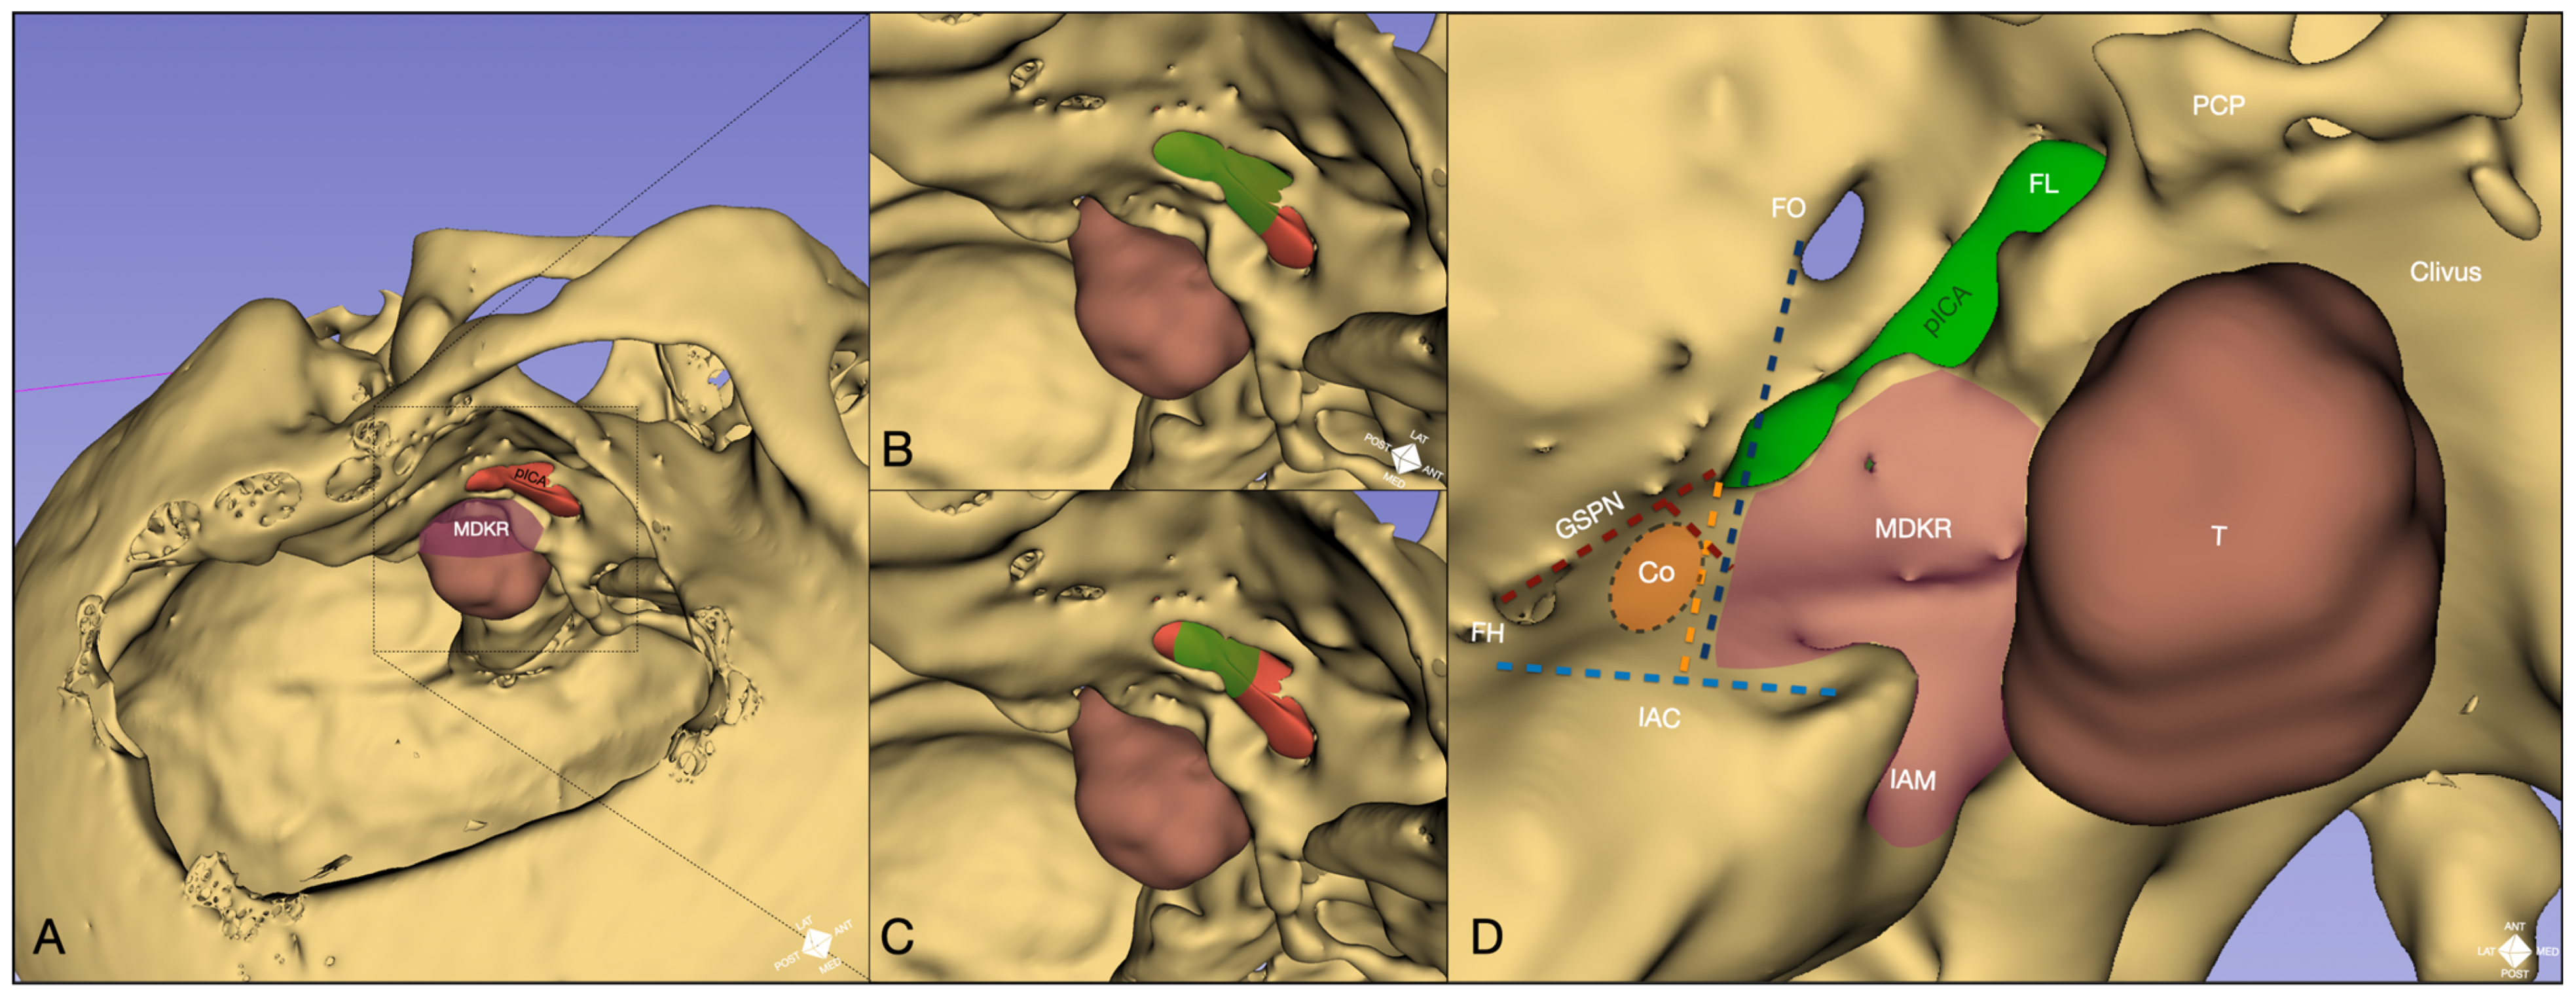

- Cochlear safety line (CSL): Defined as the perpendicular line connecting the lateral rim of the foramen ovale to the transition fold between the roof and anterior wall of the internal acoustic canal (IAC). This line laterally delineates the cochlea [10].

- Petrous ICA (pICA): Identified using intraoperative ICGva.

- Cochlear line (CL): Projected perpendicularly from the petrous ICA–GSPN intersection (measured during ICGva) onto the IAC. This line marks the lateral position of the basal cochlear turn [11].

- Carotido-cochlear distance (CCD): Adapted from Dew et al., measured as the distance between the medial ICA wall (defined with ICGva) and the geniculate ganglion at the fallopian hiatus [12]. Probing through the hiatus or GSPN electrical stimulation with facial nerve EMG confirmation refined this measurement. A 7 mm distance from the geniculate ganglion crotch was designated the safest boundary for identifying the basal cochlear turn [12].